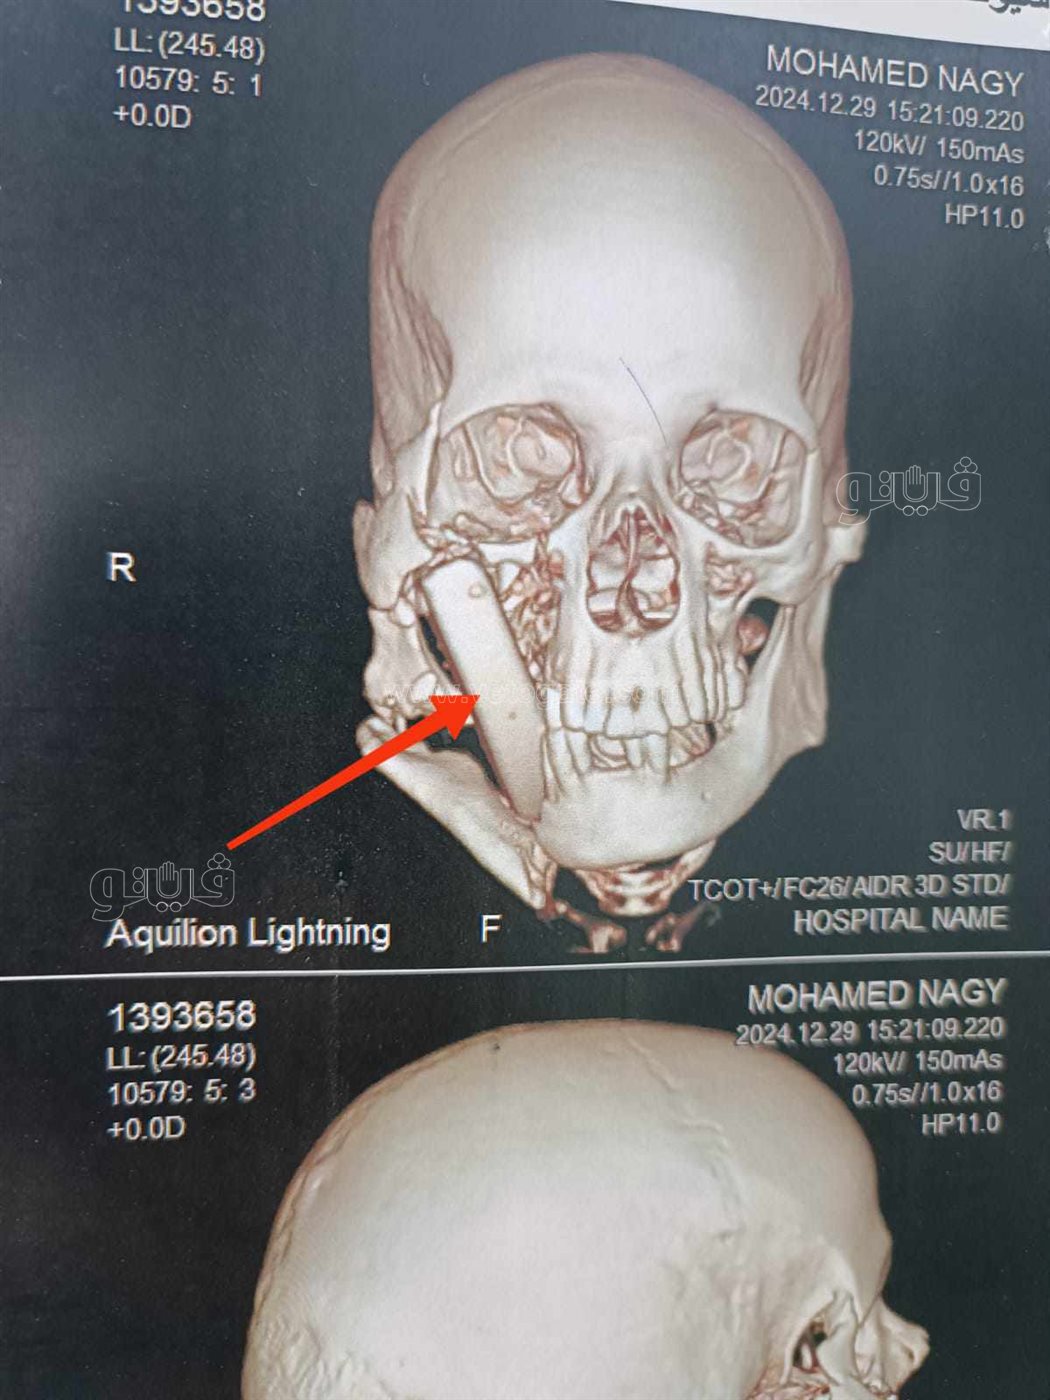

وكان مستشفي الإصابات الجامعي الجديد؛ استقبل مريضًا يبلغ من العمر ٥٠ عامًا، بعد تعرضه لإصابة بالغة أثناء أداء عمله بإحدى المناطق الحجرية، والذي نتج عنه تطاير قطعة حجرية كبيرة ارتطمت بوجه المصاب، وتسببت في حدوث تهتك بأنسجة الشفاه العلوية، واستقرت داخل أنسجة الخد الأيمن، مسببةً جروح بالغة؛ بالخد الأيمن، وقناة الغدة النكافية اليمنى، وسقف الحلق والبلعوم، كما تسبب فى كسور متعددة بعظام الوجنة اليمنى، والفك السفلى.

وتمكّن الفريق الطبي، بوحدة جراحات الوجه والفكين والرقبة؛ من تحضير المريض، والتدخل السريع؛ لإجراء جراحة عاجلة بعد عمل التجهيزات اللازمة، والإسعافات الأولية، ونجح الفريق في إصلاح أنسجة الخد، والفم، والبلعوم، مع استقرار الحالة الصحية للمريض بشكل جيد جدًا، ويتم تجهيز المريض لمرحلة جراحية لاحقة؛ لتثبيت كسور الوجه.